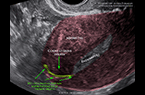

Corps jaune gravidique à 5,5 SA Corps jaune gravide à 5,5 SA Corps jaune gravide à 5,5 SA

Corps jaune gravide à 5 SA Corps jaune gravide à 5 SA Corps jaune gravide à 5 SA

Vascularisation du corps jaune analysée par Doppler-Energie en 3D Vascularisation du corps jaune analysée par Doppler-Energie en 3D Vascularisation du corps jaune analysée par Doppler-Energie en 3D

Vascularisation du corps jaune analysée par Doppler mode Dynamic Flow, en 3D Vascularisation du corps jaune analysée par Doppler mode Dynamic Flow, en 3D Vascularisation du corps jaune analysée par Doppler mode Dynamic Flow, en 3D